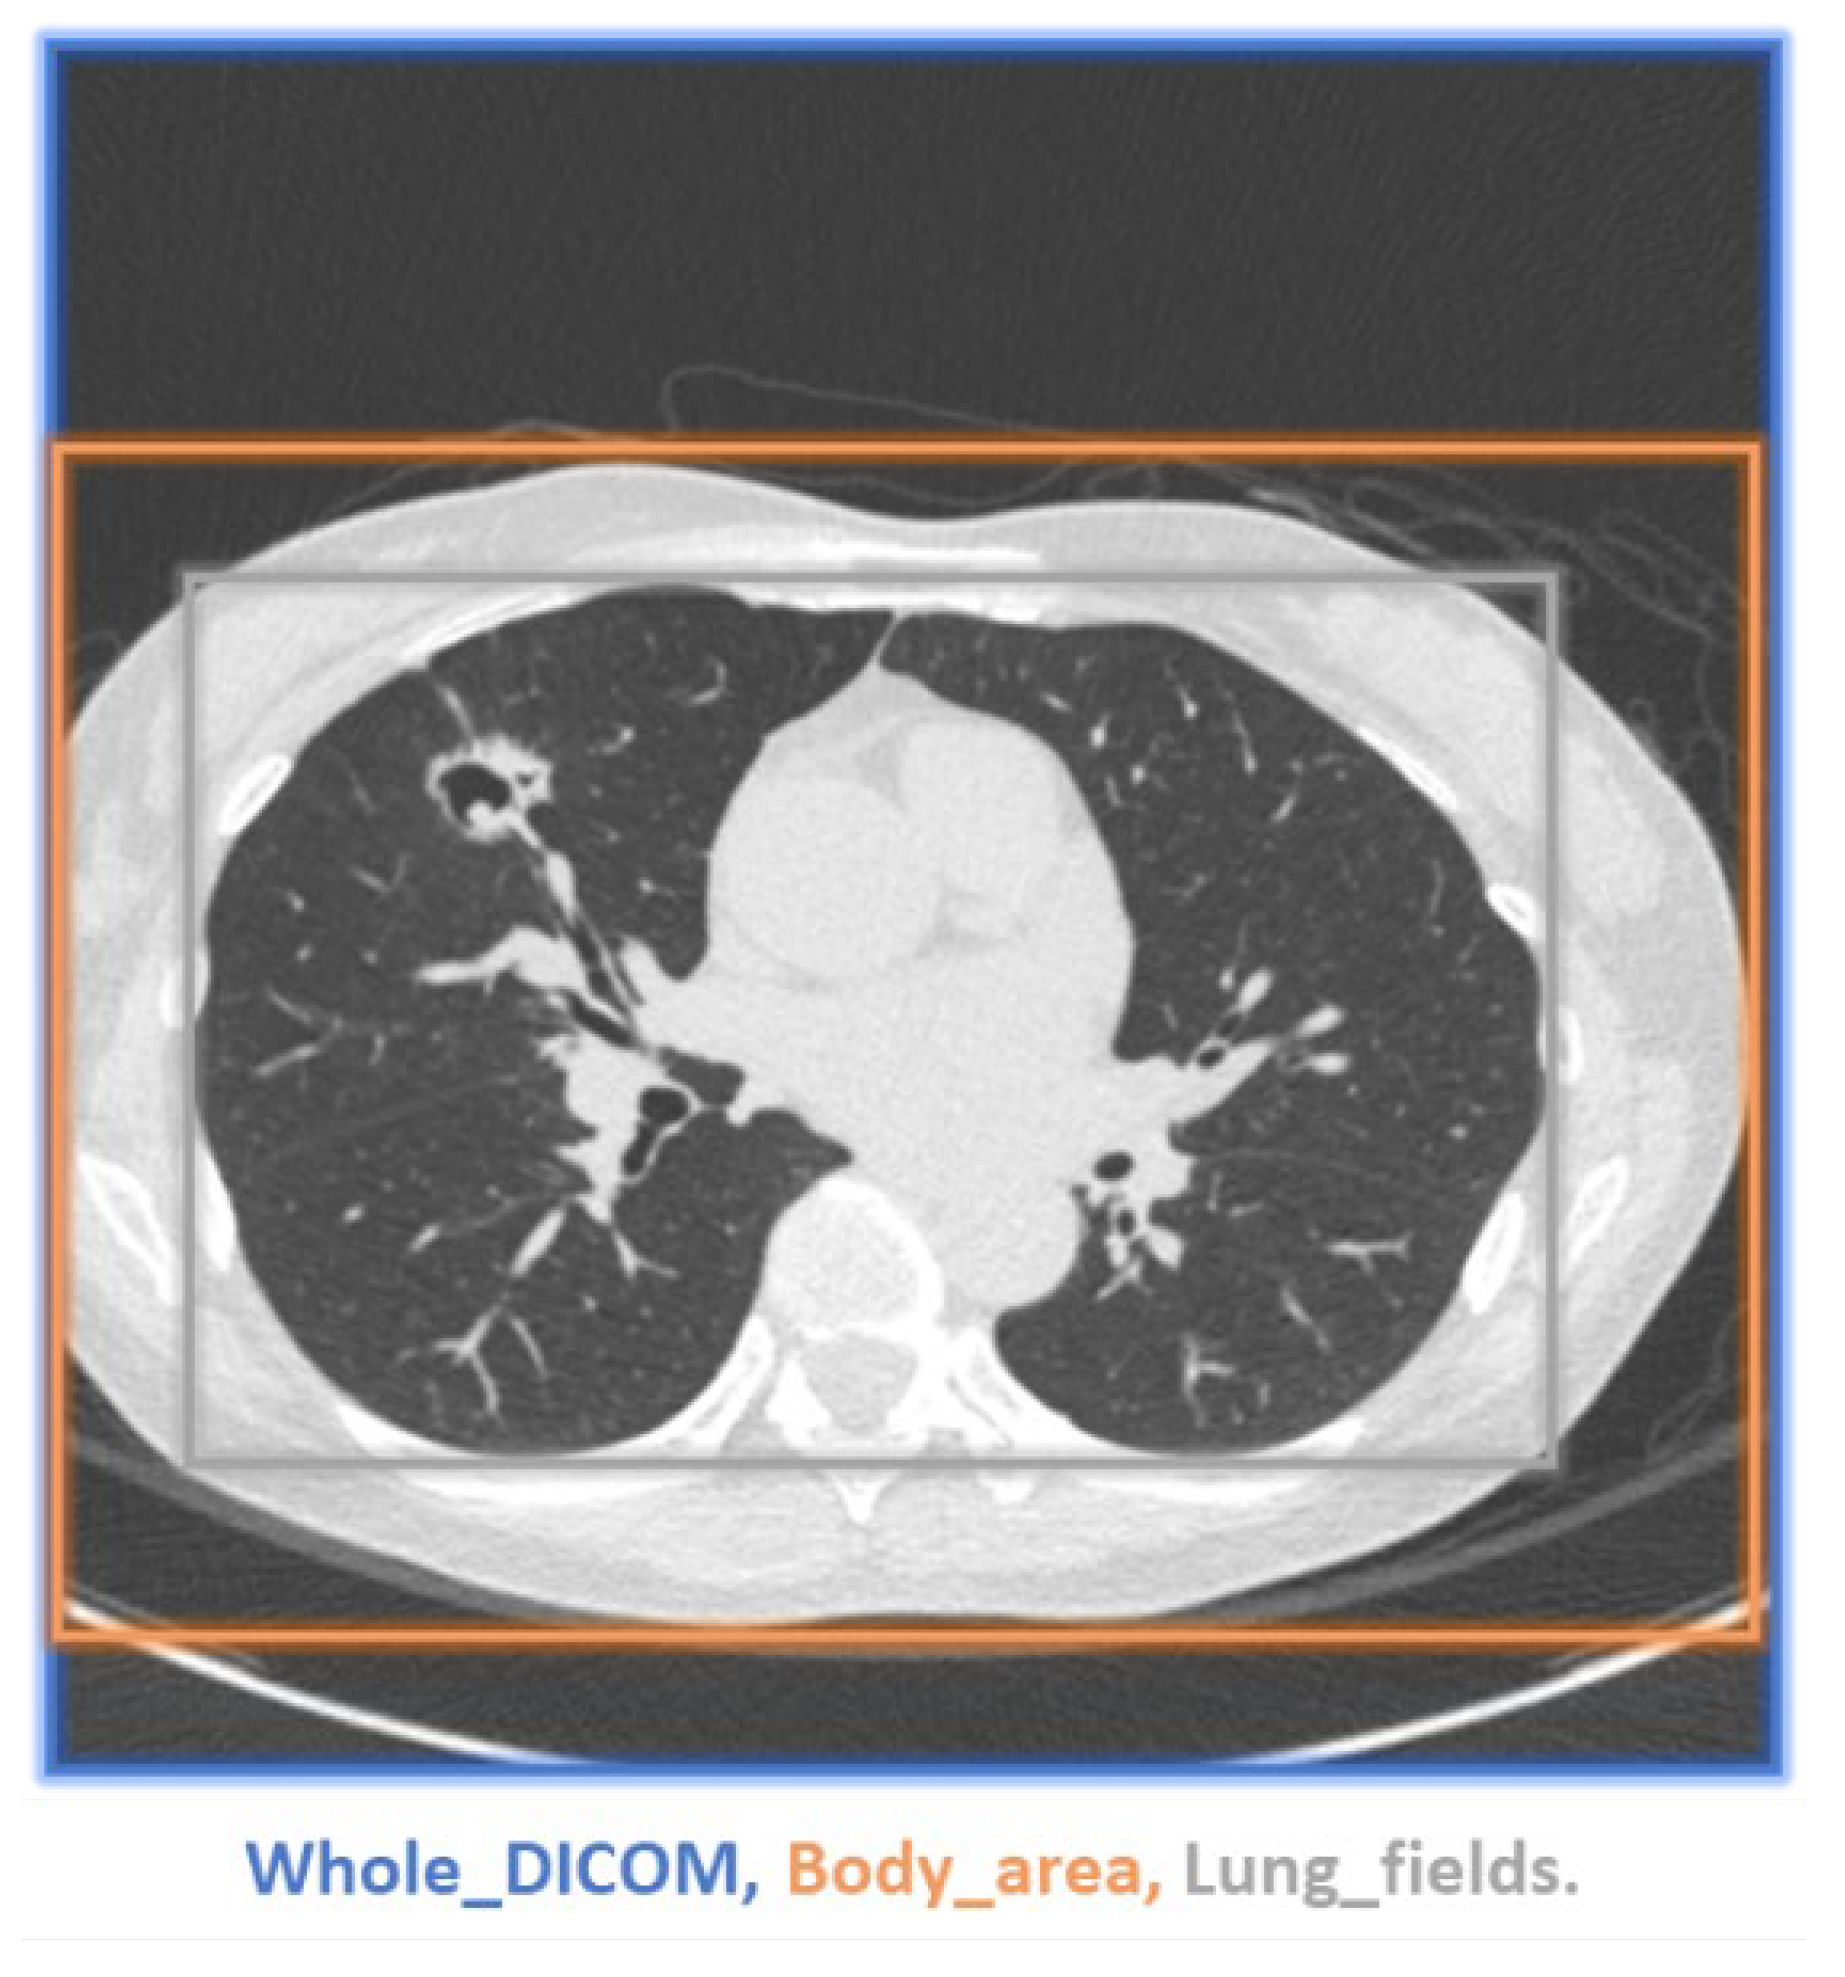

2.3. Image Preprocessing Process